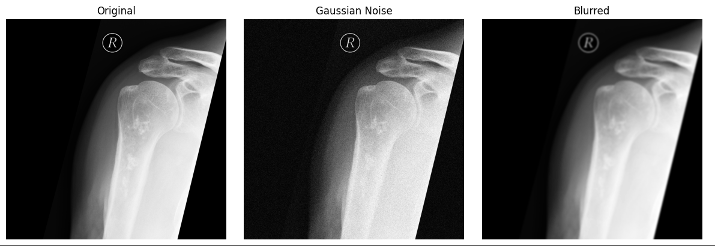

To assess model robustness, we simulated real-world distribution shifts. We introduced three perturbation scenarios to the test set: (1) sensor noise, modeled by adding Gaussian noise; (2) reduced image quality, simulated via image blurring; and (3) variations in acquisition settings, mimicked by modifying brightness and contrast. Model performance was evaluated on test dataset using classification metrics, including accuracy, sensitivity, and specificity. For sensitivity and specificity calculations, we considered Enchondroma as the negative class and ACT as the positive class.

Discussion and conclusions: Our results highlight the challenges of AI bias in bone tumor classification, with models trained on single-center data failing even under very small distribution shifts (Figure 1 [Abb. 1]). The strong reliance on dataset-specific features raises concerns about their reliability in broader clinical settings. To improve robustness and generalizability, multi-center data sharing is essential for developing accurate AI-based diagnostic tools.